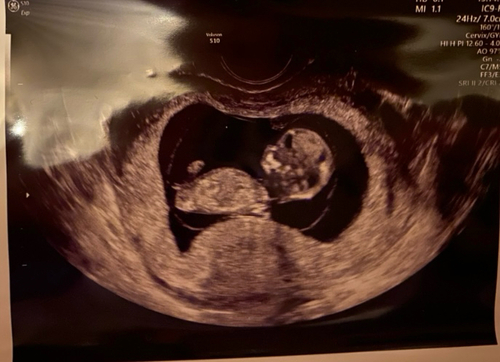

Heeft iemand een idee?💙💗 Bijna 12 weken echo (inwendig)

Denk dat je te vroeg bent, maar ik zou zeggen meisje!